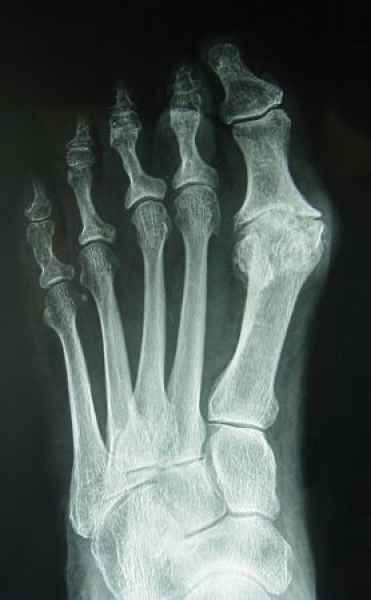

El pie es el órgano distintivo y característico de la especie humana, la única criatura que marcha erguida. El pie es una muy compleja estructura de arquitectura perfecta, adaptado a su función de apoyo, traslación, salto, con una riquísima sensibilidad que le permite detectar las más leves imperfecciones del suelo para estabilizar la marcha.

Tanto la estructura del pie como su funcionalismo que es la marcha, pueden ser asiento y manifestación respectivamente de alteraciones locales ó sistémicas, por lo que su cuidadoso examen resulta de extrema utilidad diagnóstica.